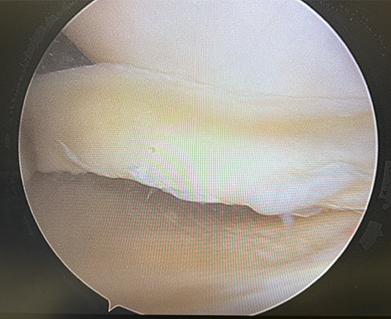

There are a few ways to help fix the meniscus to get your knee on the path to start feeling better and prevent the faster wear and tear to your knee. The way we fix the tear depends on the type and location of the tear. If the tear is able to be repaired, then we use stitches inside the knee to sew the tear back together. This will allow the meniscus to heal and restore its normal shape. Figure 1 shows a bucket handle tear of the meniscus. In this case, we opted to repair the meniscus (Figure 2) to restore knee biomechanics. If the tear is not able to be sewn back together, then we trim the edges and smooth out the meniscus similar to trimming a hangnail on your finger.

Figure 1